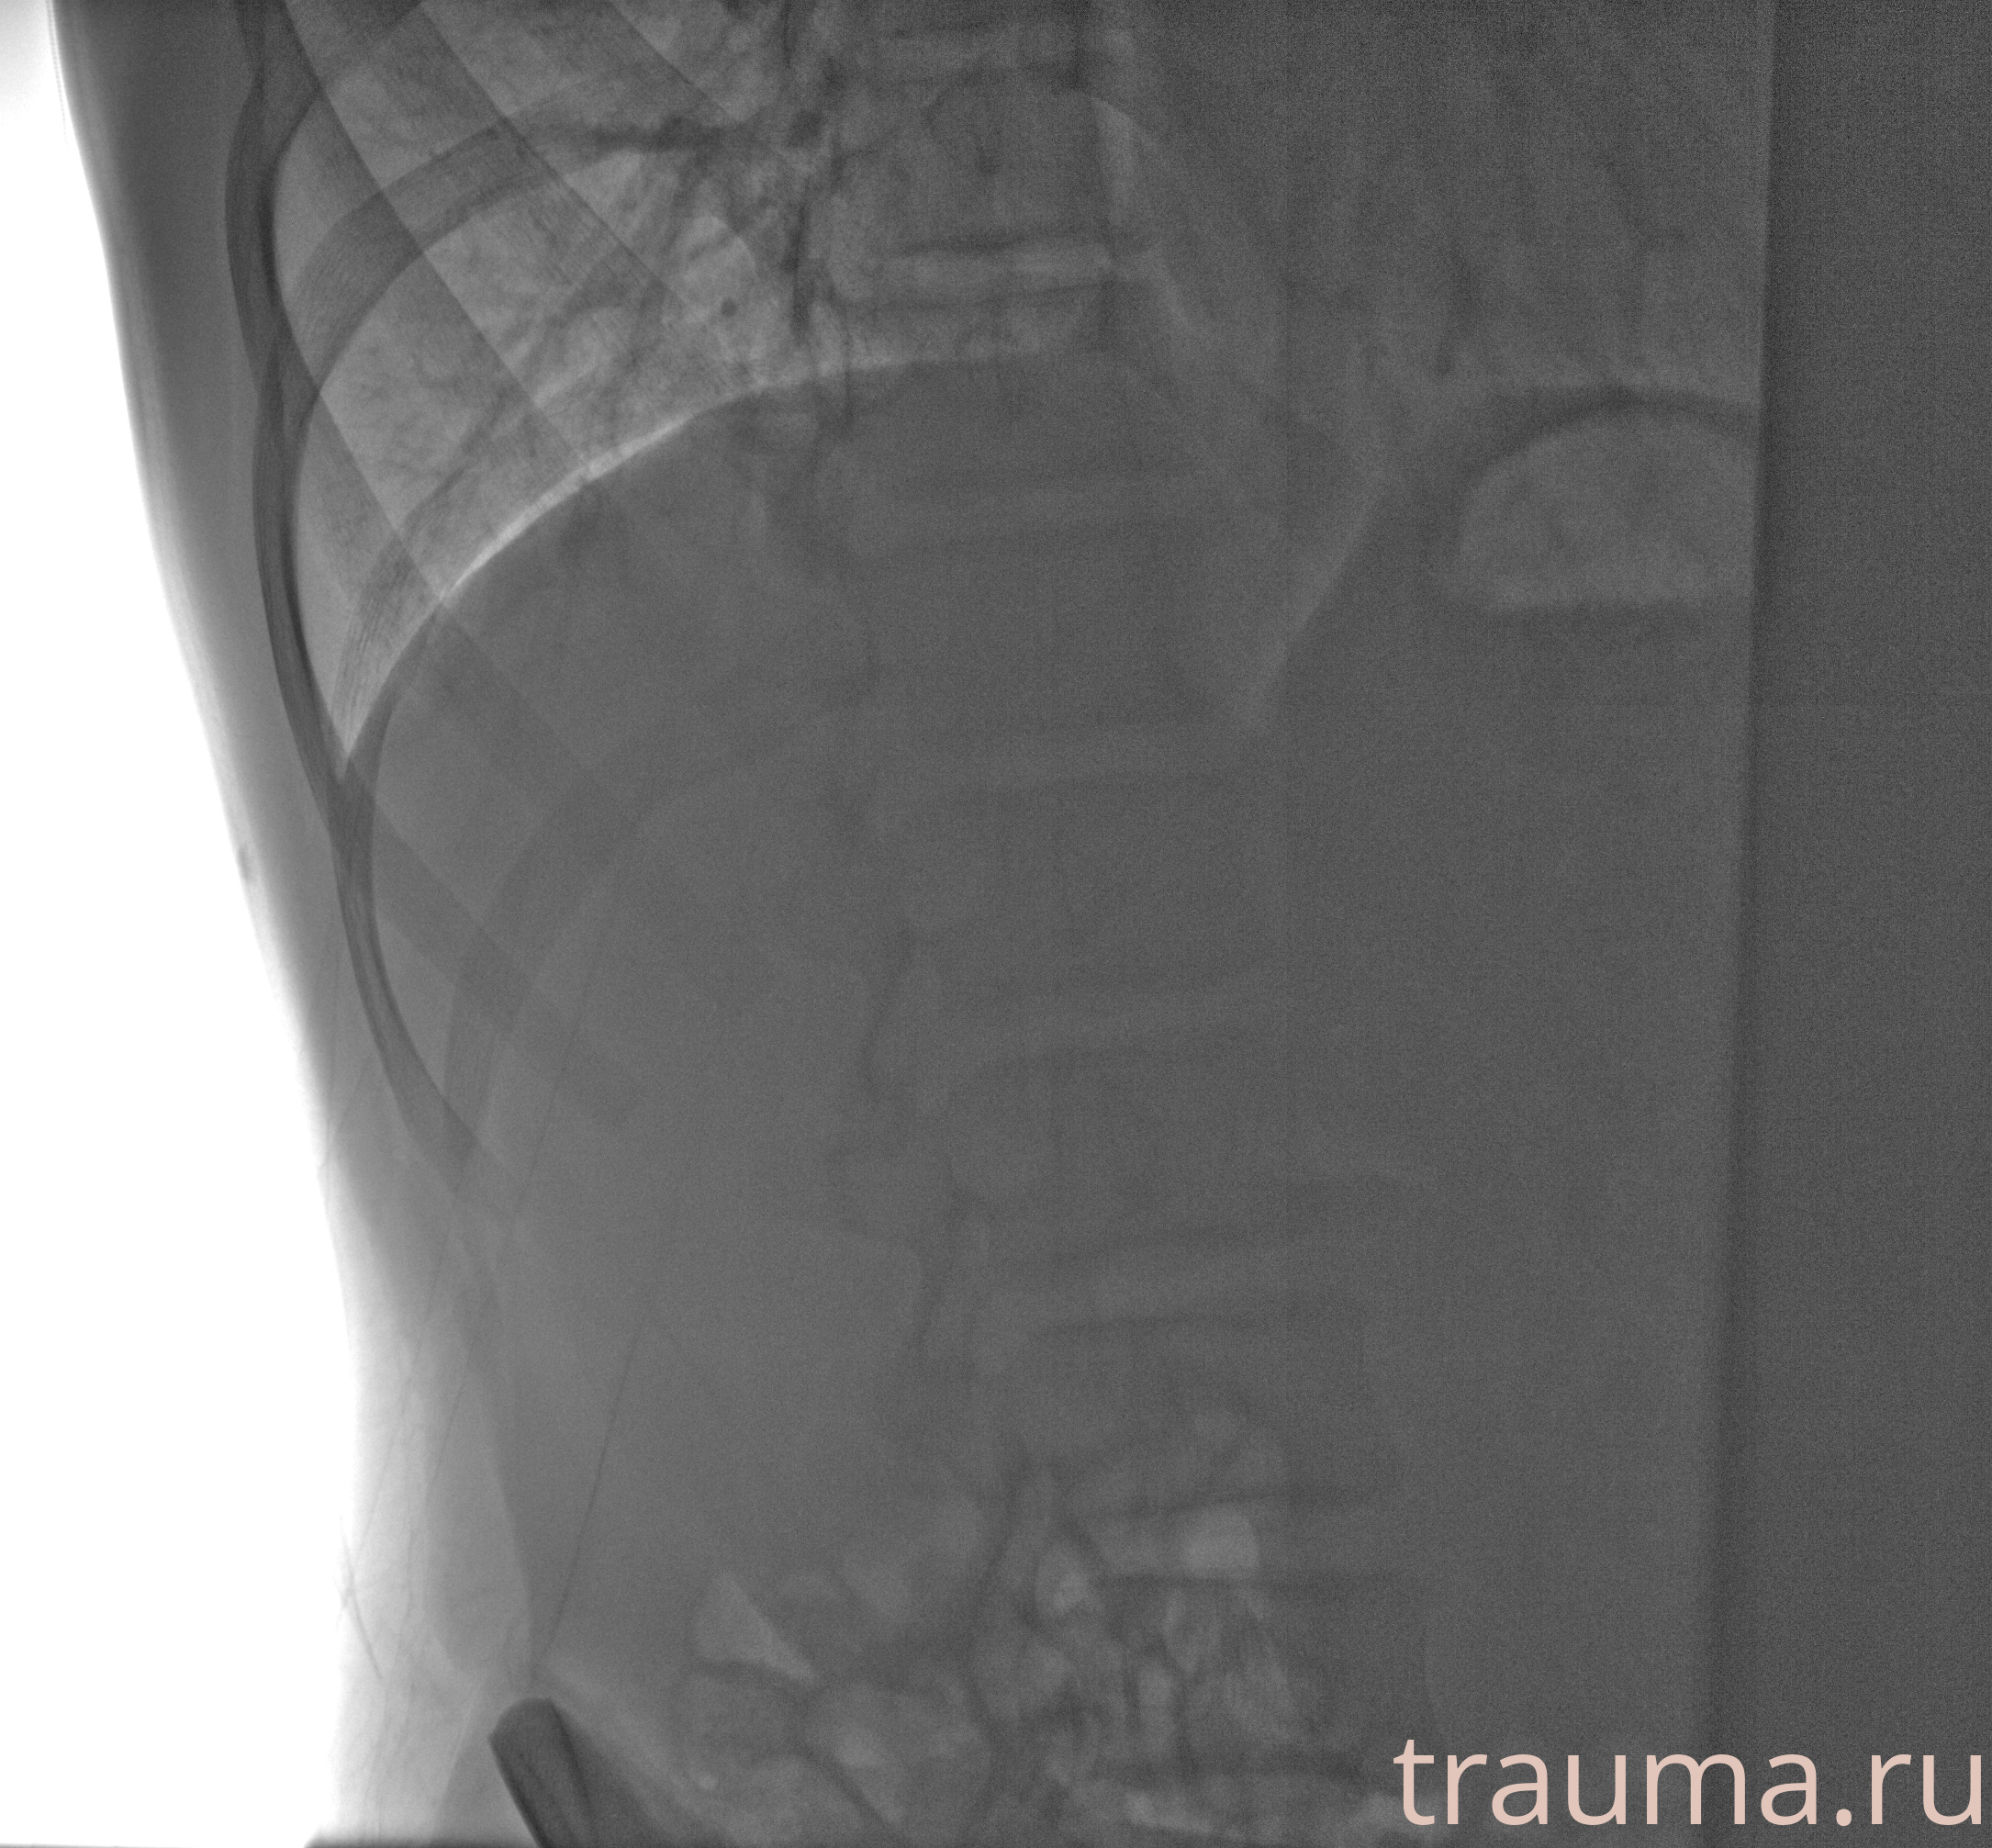

Рентгенограммы

Рентген на дому: по вашему адресу приезжает врач-рентгенолог, травматолог-ортопед с мобильным рентгеновским аппаратом, проводит диагностику травмы или заболевания, делает необходимые рентгенограммы, дает рекомендации по дальнейшему лечению. Получить качественные снимки в домашних условиях возможно благодаря уникальной методике, разработанной МосРентген Центром для института  Склифосовского